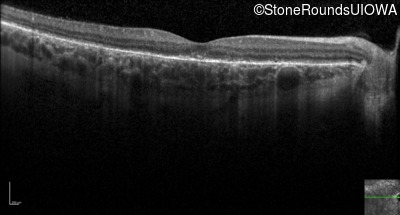

Infrared Fundus Photograph - Left - 20/60 +2 sc

Exemplar